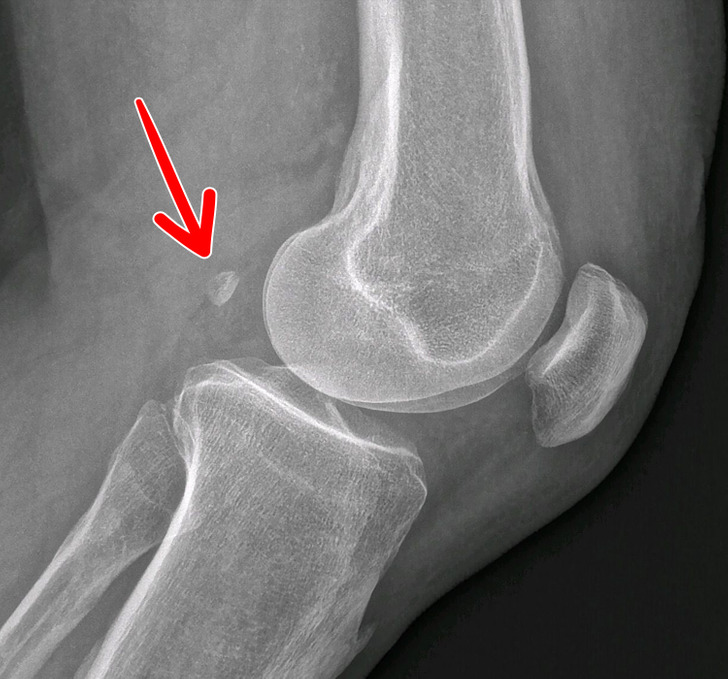

۹- تنها ۳۹ درصد از مردم دنیا یک استخوان اضافه در زانوی خود دارند

این استخوان نه تنها بی فایده است و کاربردی ندارد، بلکه باعث ابتلا به آرتروز هم می شود. به این استخوان لوبیاچه یا فابلا (Fabella) گفته می شود و وجود آن هیچ دلیل تکاملی ای ندارد. این استخوان در تاندونی وجود دارد که عضله را به استخوان ران متصل می کند. اعتقاد بر این است که این استخوان یک نیروی نابرابر به زانوها وارد و احتمال وارد شدن آسیب به غضروف را بیشتر می کند.

۱۰- تا سن ۳ تا ۵ سالگی، کشکک زانوهایمان به شکل دیگری است

بیشتر افراد فکر می کنند بچه ها بدون کشکک زانو به دنیا می آیند با این حال، نوزادان هم کشکک زانو دارند، فقط از جنس دیگری است. کشکک زانوی نوزادان به طور کامل از غضروف است. این ویژگی برای این است که بچه راحت تر از مجرای زایمان بدن مادر خارج شود. کشکک زانوها بعداً سفت و محکم می شود.